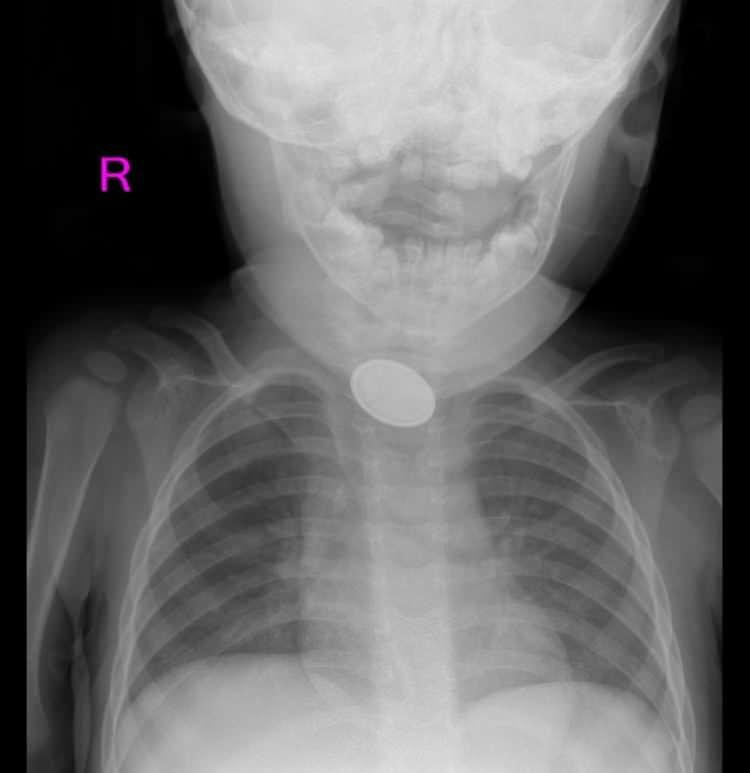

Kayseri’de 15 aylık bebeğin yemek borusuna pil ve lego parçası kaçtı

"Oyuncak olan odaya gidip, bir cisim yutmuş. 4 yaşındaki oğlum, 'Anne kardeşim lego yuttu' dedi. İlk yardım biliyorum. Müdahale ettim ama çıkmadı. 'Herhalde yuttu artık, dışkısından çıkar' diye düşündüm. Daha sonra yutma güçlüğünü gördüğümde hemen geldik. Pil de olduğunu öğrendik. Meğer önce pil daha sonra lego parçası yutmuş. Şoka uğradık. Çok korktuk. Bizim en çok korktuğumuz şey, bir şeyleri yutmasıydı. Normalde dikkat ederdik ama kaşla göz arasında olan bir şey. Bundan sonra daha dikkatli olacağız. Herkes dikkatli olsun. Çok zor bir ameliyat geçirdi. Erman hocam ve ekibi olmasa çocuğum kucağımda olmayabilirdi. Tam teşekküllü bir hastane olduğu için hemen buraya geldik. Başka bir hastane düşünmedik. Konum olarak uzağız aslında ama hemen geldik. Herkesten çok memnunuz"